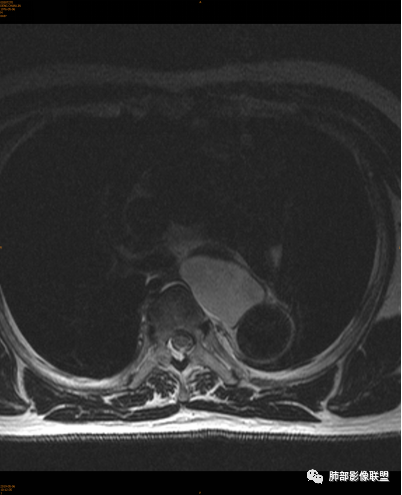

气管、左主支气管后方,食道左侧囊性占位,壁薄且均匀、光滑。气管及左主支气管受压凹陷、变形。

食道也受压变形、移位。

MR所见也差不多。